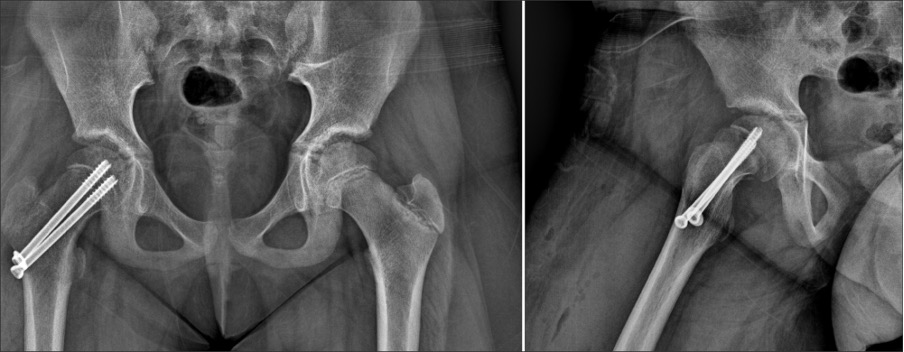

수술적 치료

· 성장판이 닫히기 전, 성장판을 관통해 대퇴골두까지 나사못을 삽입하여 더 이상의 어긋남을 방지합니다.

· 성장판이 닫힌 후, 대퇴골두가 어긋난 경우 뼈 수술을 통해 교정합니다.